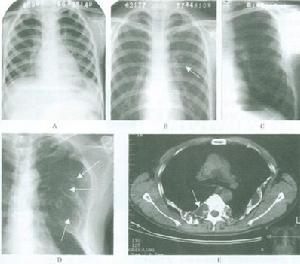

7.軟組織鈣化 軟組織鈣化(轉移性鈣化)多因持續性鈣磷沉積增高所致,可見於動脈 眼、內臟、關節和皮膚。甲狀旁腺素水平的持續升高除了引起骨病外 還可導致磷酸鈣在小動脈、關節、軟組織和內臟的沉積。當鈣磷乘積超過70時最易出現。一種更為嚴重的稱為鈣化防禦(calciphylaxis)的轉移性鈣化常伴有顯著的動脈鈣沉積和組織缺血和壞死。

放射學檢查:繼發性甲狀旁腺功能亢進的放射學改變包括骨內膜、骨皮質和骨膜下的骨吸收,終端指、趾骨的腐蝕,囊腫形成,骨膜的neostosis和骨硬化,其中骨膜下骨吸收是最常見的放射學改變,主要見於指骨, 還可見於骨盆骨、鎖骨遠端以及肋骨、尺骨、脛骨和下頜骨下方的表層。骨硬化的放射學改變,為骨的密度增加,常見於椎體 骨盆、肋骨、鎖骨和各種長骨的乾骺端, 骨軟化的診斷有賴於骨活檢。放射學的惟一發現是Loosers帶的出現和假性骨折,骨密度常降低,但不足以診斷骨軟化。骨質減少是指放射學檢查發現的骨密度減低,常見於長期腎功能衰竭做血透治療者。骨軟化、繼發性甲狀旁腺功能亢進和骨質疏鬆經放射學檢查都可發現骨密度減低,很難單憑放射性特點來判斷骨質減少的原因。